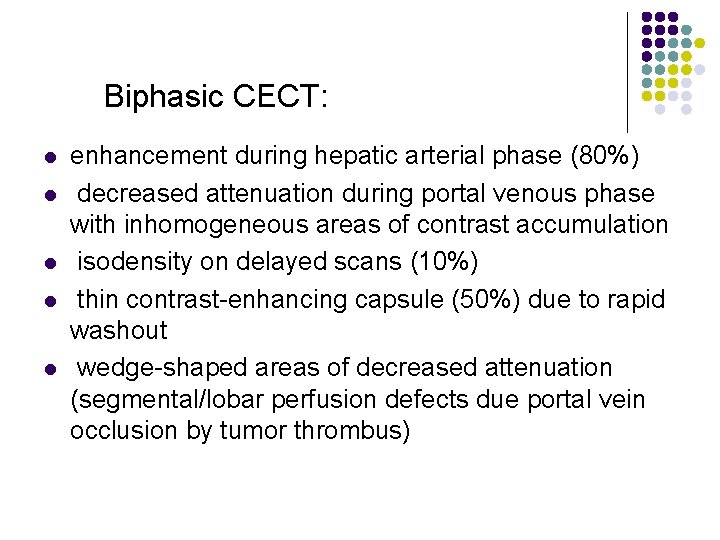

Biphasic CECT: l l l enhancement during hepatic arterial phase (80%) decreased attenuation during portal venous phase with inhomogeneous areas of contrast accumulation isodensity on delayed scans (10%) thin contrast-enhancing capsule (50%) due to rapid washout wedge-shaped areas of decreased attenuation (segmental/lobar perfusion defects due portal vein occlusion by tumor thrombus)

Biphasic CECT: l enhancement during hepatic arterial phase (80%)

Biphasic CECT: l decreased attenuation during portal venous phase with inhomogeneous areas of contrast accumulation

Biphasic CECT: l isodensity on delayed scans (10%)

Biphasic CECT: l enhancement during hepatic arterial phase (80%)

Biphasic CECT: l decreased attenuation during portal venous phase with inhomogeneous areas of contrast accumulation

Biphasic CECT: l isodensity on delayed scans (10%)